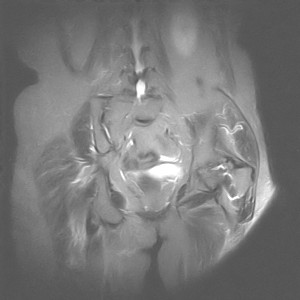

图像太差了 1、右侧臀肌旁脓肿? 建议增强 2、左侧股骨头坏死并半脱位

1、左侧股骨头坏死并髋关节半脱位;

2、右侧臀肌感染,(可能褥疮所致)